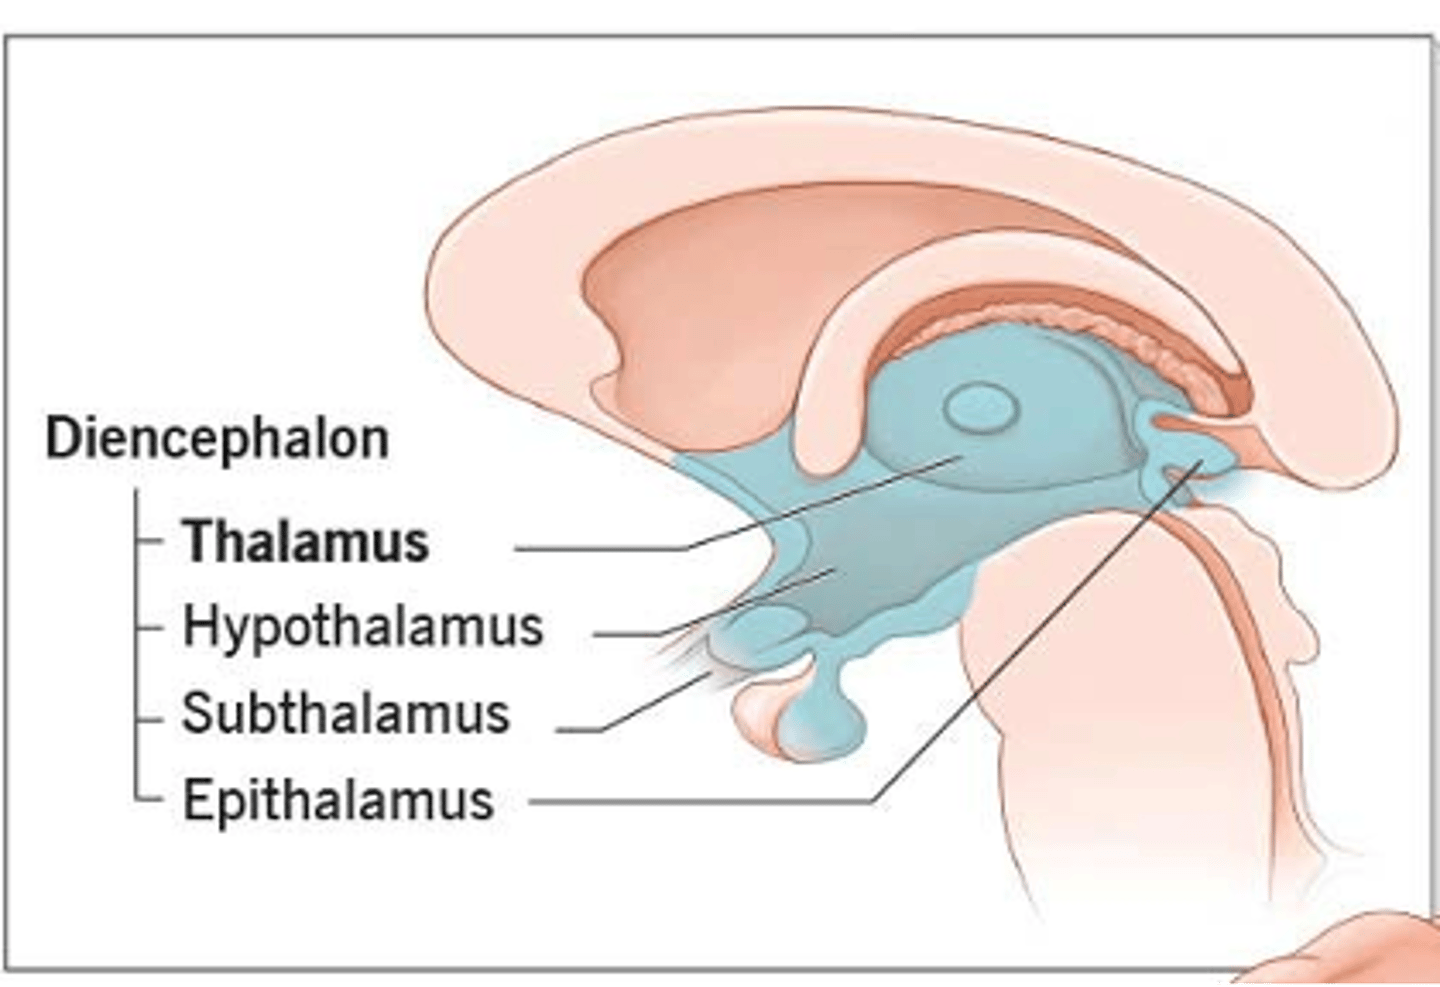

what are 2 important structures of the diencephalon?

1. thalamus

2. hypothalamus

what structure of the diencephalon regulates the of flow sensory and motor information from various location that will ultimately reach the cortex?

thalamus

what structure of the diencephalon is the relay station for all but one sensory tracts on their way to the cortex? what is the exception?

thalamus

olfactory is the only tract to bypass the thalamus and go directly to the cortex

what are 2 key thalamic nuclei?

1. ventral posterolateral nucleus (VPL)

2. ventral posteromedial nucleus (VPM)

what structure of the diencephalon is the main visceral control center of the brain?

hypothalamus

what structure of the diencephalon mediates a wide range of functions through connections with endocrine, autonomic, somatic motor, limbic systems, and maintaining a state of homeostasis?

hypothalamus